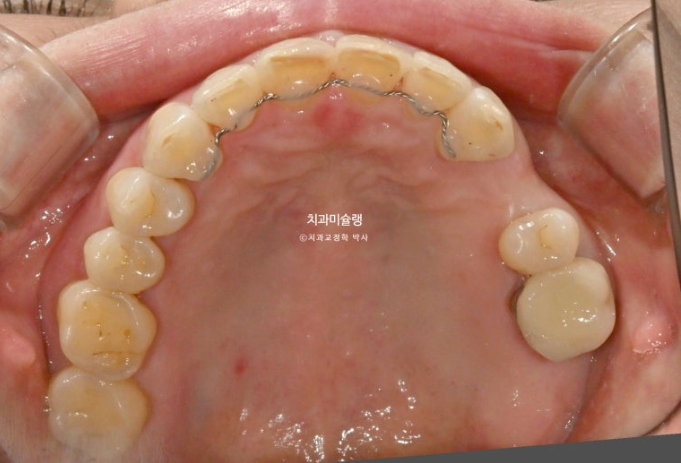

24년 7월 50대 환자분께서 교정치료를 위해 오셨습니다.

앞니가 세로 길이보다 가로길이가 더 긴, 한마디로 납작한 형태입니다.

치아 사이사이 벌어진 틈을 레진으로 메꿔놓고 지내온 것입니다.

충치로 인해 어금니들을 발치하게 되면서 교정치료를 병행하고자 오셨습니다.

일단 앞니 사이사이 레진을 제거해 보았습니다.

아래 앞니 사이 치석도 같이 제거합니다.

레진이 차지하는 비중이 컸습니다

아래 앞니 사이사이는 공간이 없는 데 위 앞니 사이사이에만 큰 공간이 있다면

이 공간을 교정으로 100% 메꿀 수 없습니다.

최대한 공간을 줄여놓고 남은 미세공간은 레진으로 마무리 해야 합니다.

인비절라인 라이트 치료 권유드렸습니다.

아래 앞니는 원래 있던 블랙트라이앵글을 없앨 겸 치간삭제를 동반하기로 합니다.

또한 아래 앞니가 위 앞니를 밀어내어 위 앞니 벌어짐이 심해지지 않도록 아래 앞니는 함입도 필요합니다.